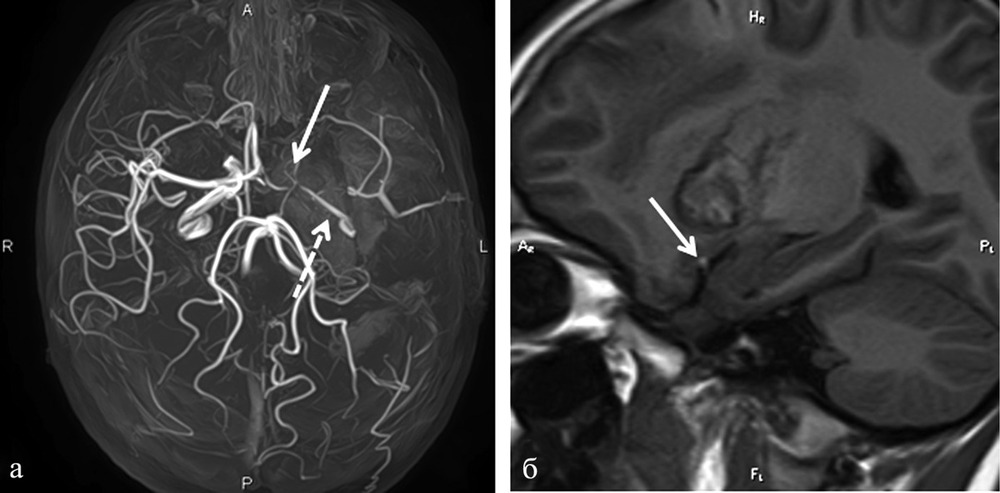

Снимки и иллюстрации микроаневризм сосудов головного мозга